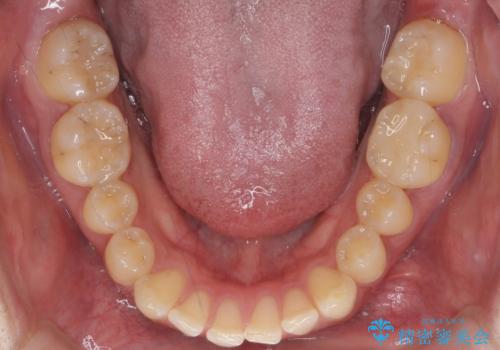

- 上下の歯のすき間を気にして来院。

患者様の歯は咬耗といって削れて短くなっていたため、セラミックでかぶせると隙間をうめるため横長の歯になりそうでした。術後の見た目は矯正の方が自然にみえるとお伝えしました。

インビザライン(マウスピース矯正)は小さな隙間を閉じるのは得意です。

ただし、上に隙間が余っている状態ですと、ただ閉じようとしても上の前歯が中に入らないと隙間が閉じないため、下の歯の位置によっては隙間が閉じ切れなくなります。

その場合は下の歯を上の前歯から離す方向に圧下したりする動きが必要になり、全体矯正が必要になります。